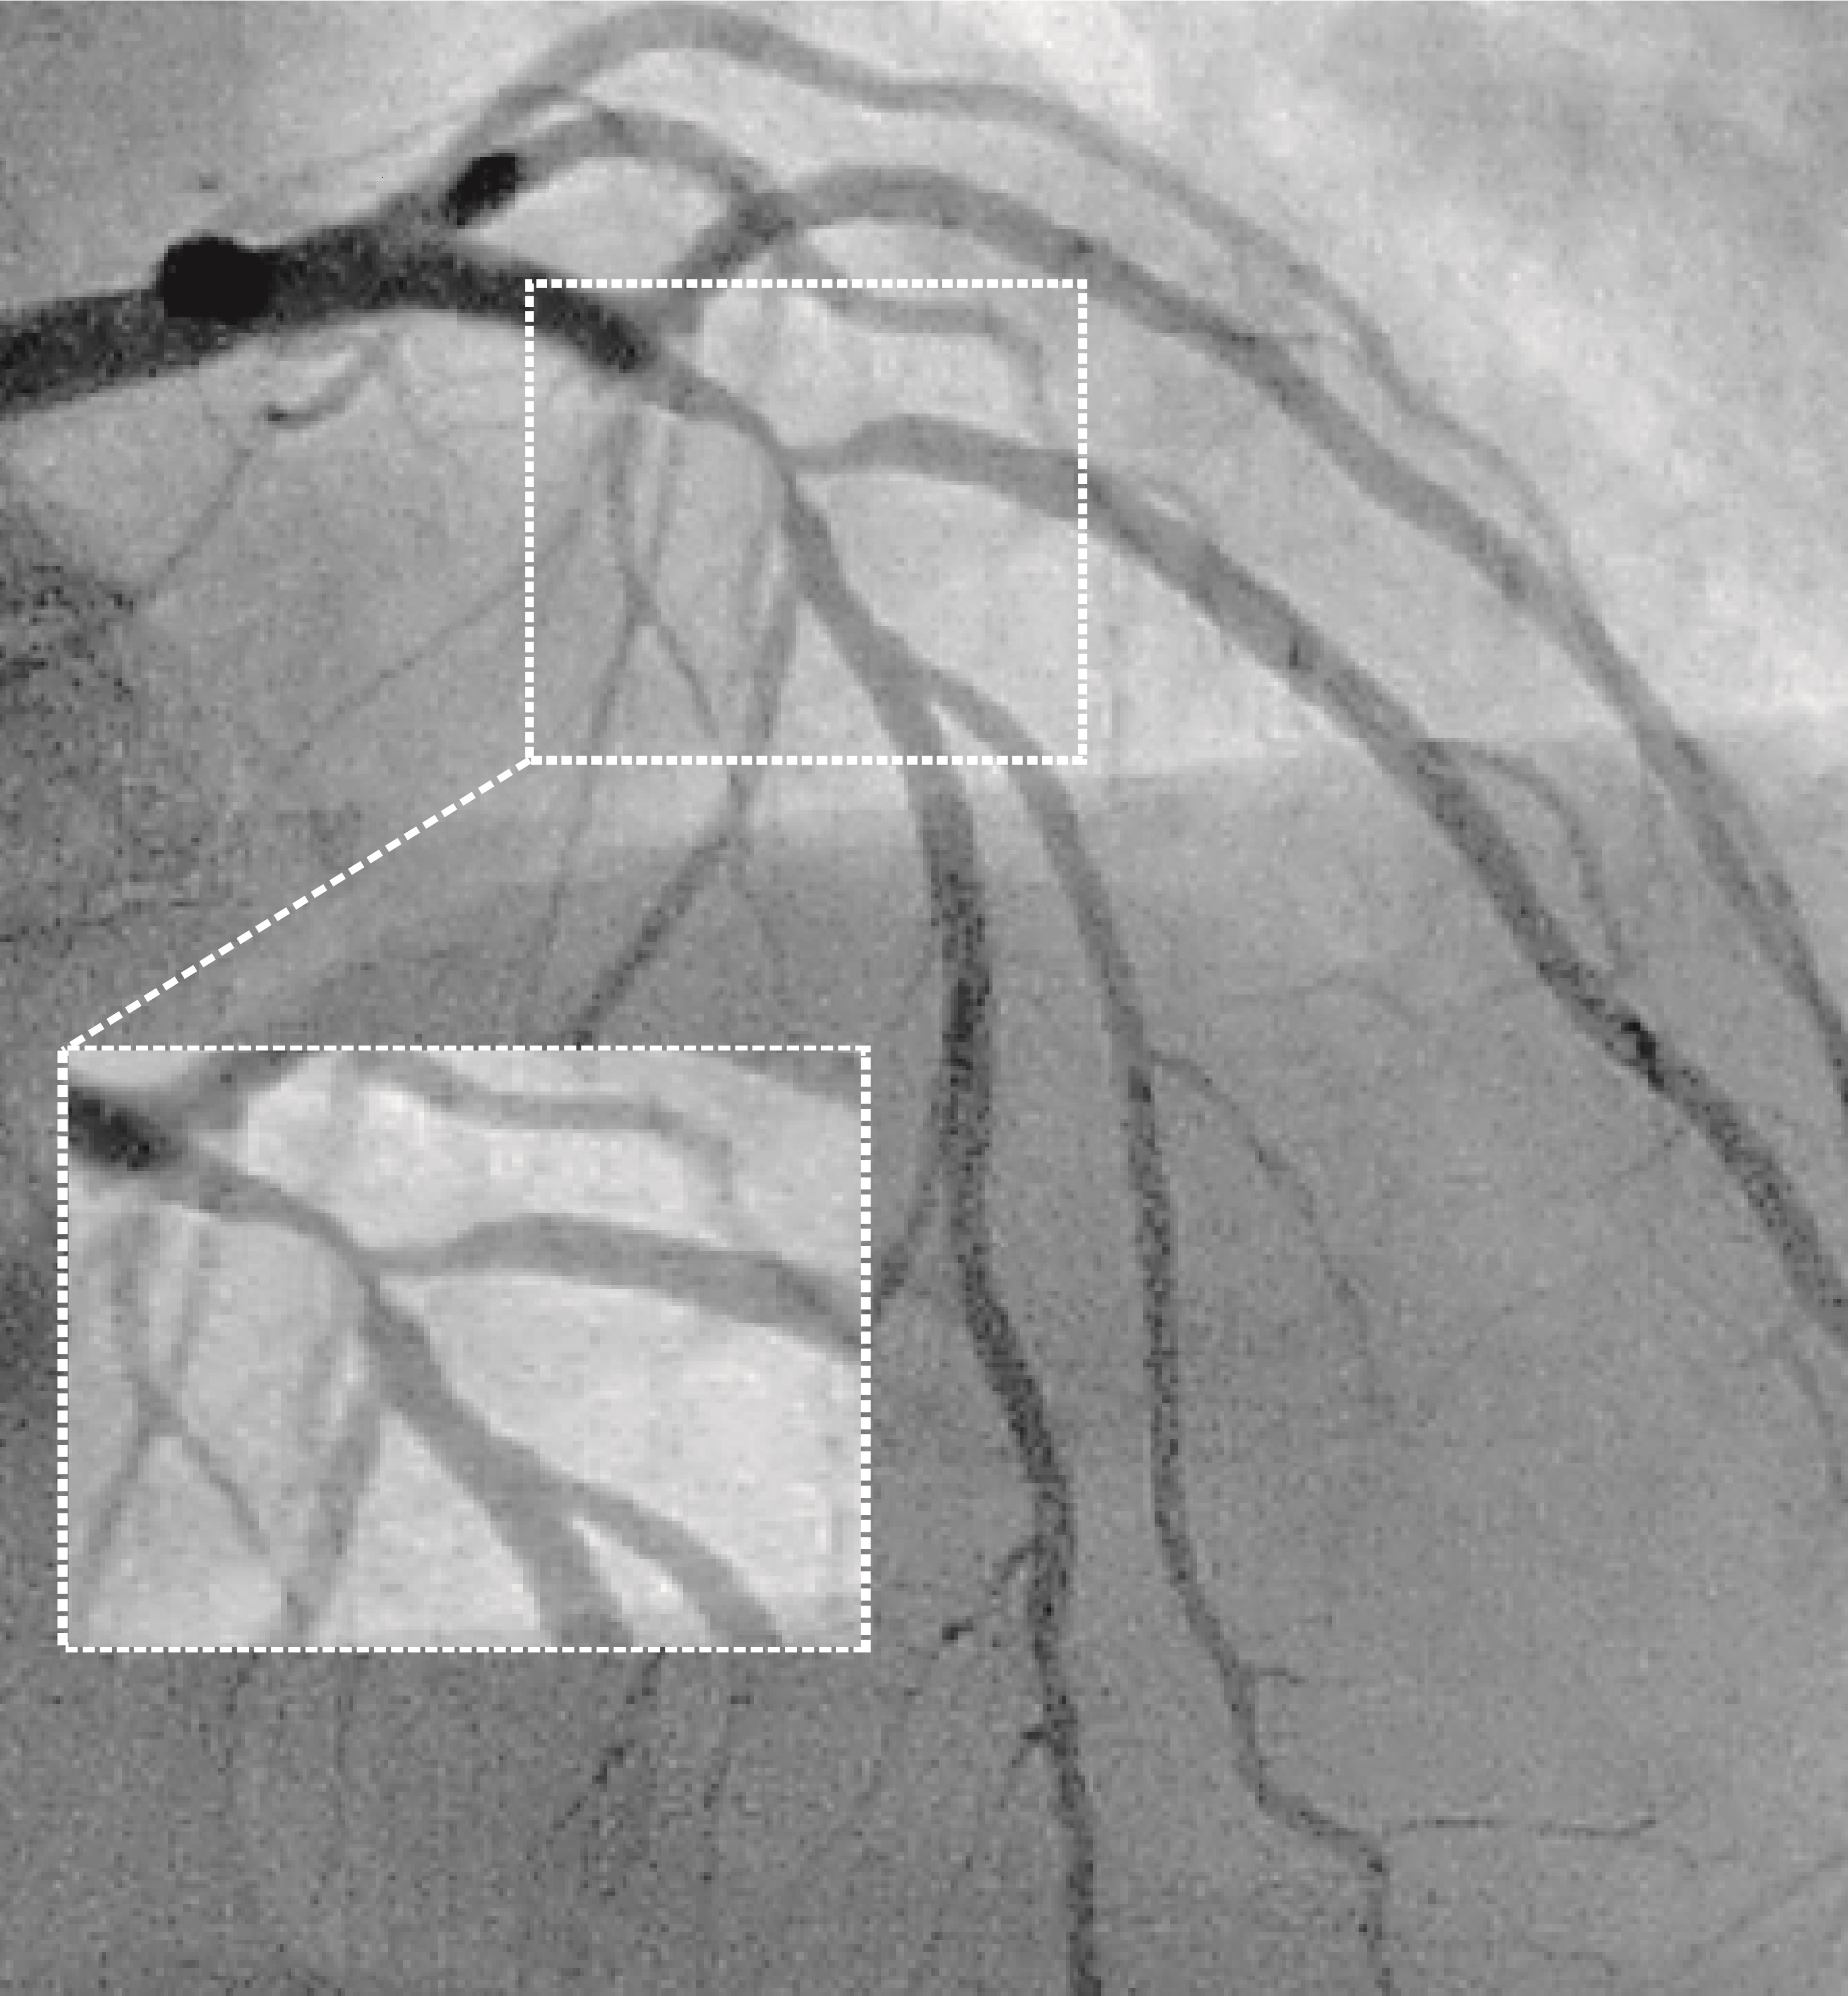

A novel framework for fluid/structure interaction in rapid subject-specific simulations of blood flow in coronary artery bifurcations

Abstract PDF FIG 1 Odgovor recenzentu A Rezime rada ID 2792 A NOVEL FRAMEWORK FOR FLUID/STRUCTURE INTERACTION IN RAPID SUBJECT-SPECIFIC SIMULATIONS OF BLOOD FLOW IN CORONARY ARTERY BIFURCATIONS Fig 2 Fig 3 Fig 4 Fig 5 Fig 6 Fig 7 Fig 8 Fig 9 Fig 10 -